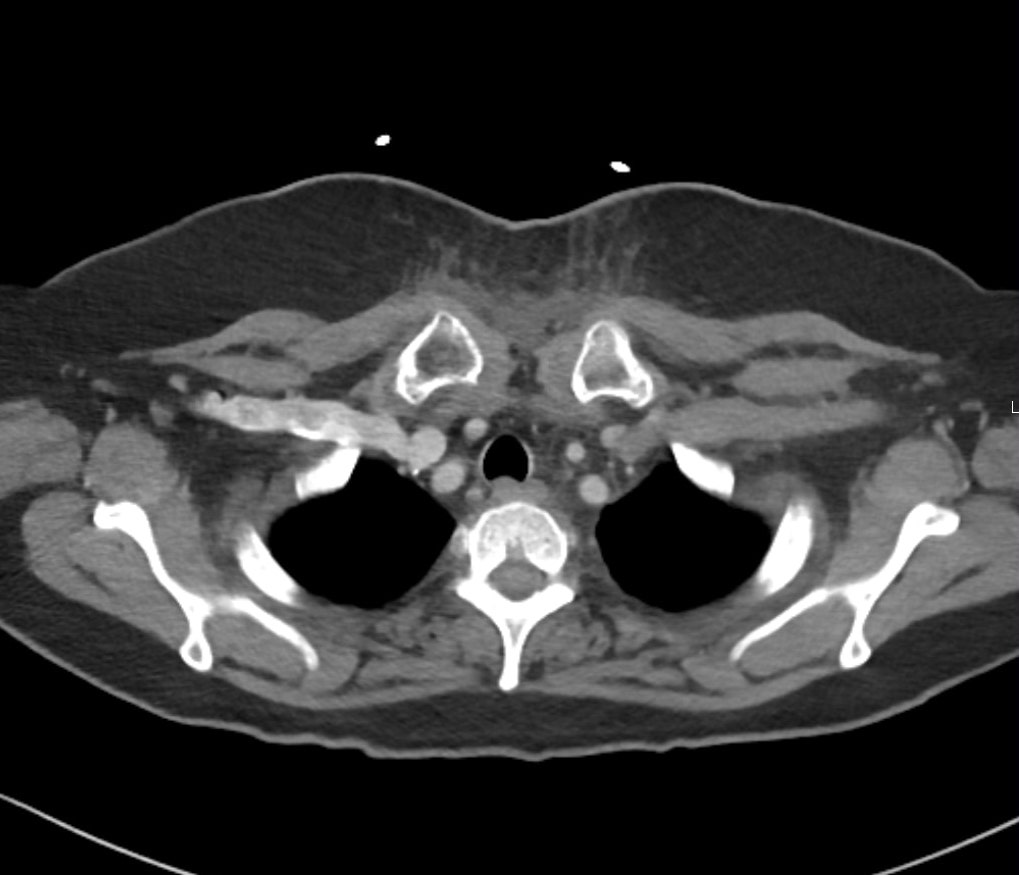

Retropharyngeal abscess (RPA) is an uncommon yet potentially life-threatening condition that is more often seen in young children and may be misdiagnosed in adults presenting with atypical features.1 Retropharyngeal abscess results from spread of antecedent upper respiratory tract infection or traumatic inoculation via foreign body ingestion or medical instrumentation. Clinically, RPA may present with fever, pharyngitis, neck pain, and dysphagia. Diagnosis is often confirmed with imaging studies. We present a case of a 66-year-old female with asthma, hypertension, and gastroesophageal reflux disease (GERD) who presented to the emergency department (ED) for evaluation of neck fullness, shoulder pain, dysphagia, and abdominal pain starting less than 24 hours prior to presentation. Computed tomography (CT) revealed a prevertebral/retropharyngeal fluid collection from the odontoid tip to the C4 vertebral body measuring 5.4 × 1.0 × 3.3 centimeters (cm) in size with associated edema at the left neck base extending into the upper chest, suggestive of retropharyngeal abscess. The patient received intravenous (IV) vancomycin and piperacillin/tazobactam and was transferred to a higher level of care for otolaryngologist evaluation. The patient remained stable without airway compromise while in our department. This case underscores challenges in diagnosing atypical presentations of RPA in adults, emphasizing timely recognition to prevent complications.